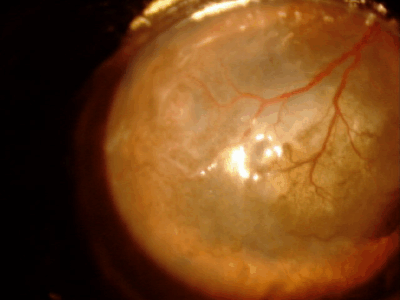

血管新生

角膜には本来血管がなく透明ですが、炎症、傷、刺激などが慢性化すると角膜周囲から血管が伸びてきます。だいたい1日あたり1mm伸びるといわれています。原因としては角膜炎、角膜潰瘍、乾性角結膜炎(ドライアイ)、パンヌスなどがあります。